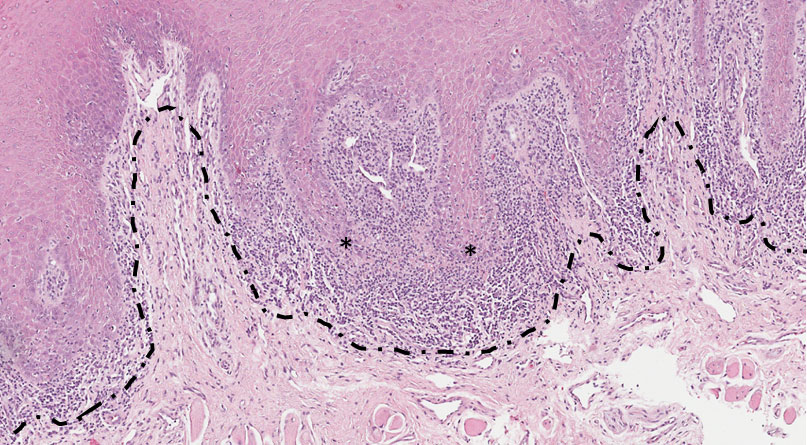

Fragmento de mucosa bucal revestida por tecido epitelial hiperplásico (Figura 7 seta) com focos de acantose e hiperceratose (Figura 7 — asterisco), perda de nitidez da camada basal (Figura 8 asterisco e Figura 9 seta) e infiltrado inflamatório mononuclear em banda justa epitelial (Figura 8 — delimitado pelo tracejado e Figura 9).

Dados importantes para o diagnóstico

Observar as projeções do tecido epitelial (“dentes em serra”), tecido hiperplásico e com hiperceratose (aumento da camada de ceratina), infiltrado inflamatório crônico predominantemente de linfócitos subjacente ao tecido epitelial e apagando (destruindo) a camada basal.

Figura 7

Figura 8

Figura 9